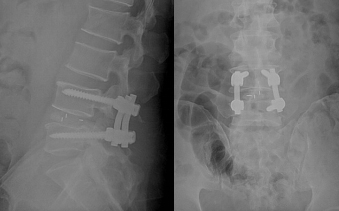

患者术后3天即顺利拔除伤口引流管并离床活动,感觉双下肢疼痛程度较术前有明显缓解;术后1周出院时已可连续步行20分钟仍未出现明显腰腿痛症状;术后6周复查时,患者对治疗效果非常满意,他表示,术前腰腿痛症状基本消失,个人的精神状态和自信心得到明显的改善和提升,又有了重新面对生活的勇气。

图4、5:患者术后影像学资料